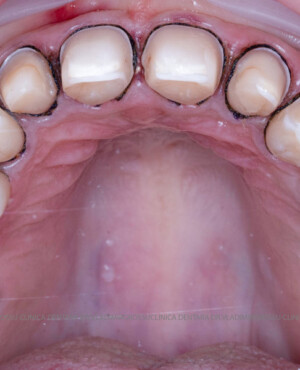

Cazuri clinice

Caz 1

Caz 2

În cazul în care pacientul pune la dispoziție fotografii vechi, acestea sunt analizate, însă adesea reabilitarea presupune crearea unui zâmbet nou, personalizat. Pacienții adesea au preferințe clare privind forma și aspectul dinților viitorului zâmbet, iar echipa medicală depune toate eforturile pentru a le respecta dorințele. Dacă este cazul, se propune un design alternativ, explicat pe larg pacientului, care, de regulă, îl acceptă. Protocolul foto-video este indispensabil pentru realizarea unor astfel de lucrări.